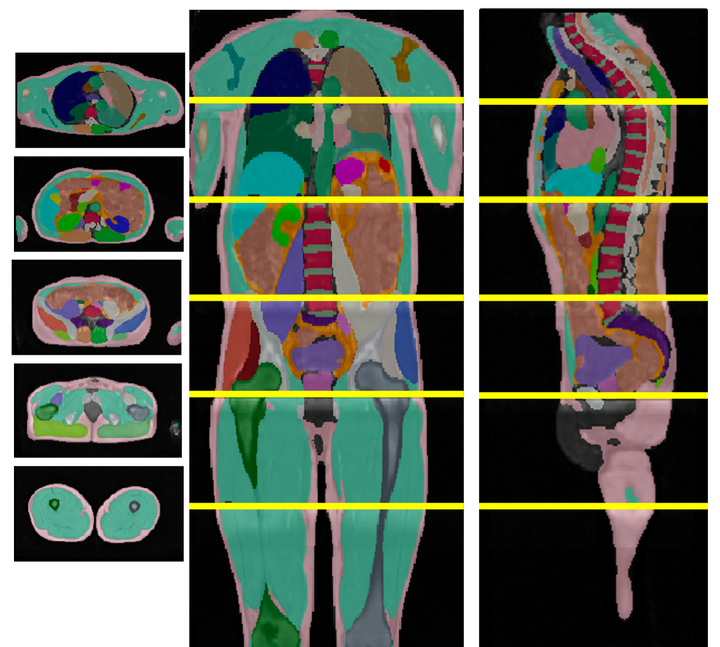

In medical imaging, the primary challenge is collecting large-scale labeled data due to privacy concerns, logistics, and high labeling costs. In this work, we present the UK Biobank Organs and Bones (UKBOB), the largest labeled dataset of body organs, comprising 51,761 MRI 3D samples (equivalent to 17.9 million 2D images) and more than 1.37 billion 2D segmentation masks of 72 organs, all based on the UK Biobank MRI dataset. We utilize automatic labeling, introduce an automated label cleaning pipeline with organ-specific filters, and manually annotate a subset of 300 MRIs with 11 abdominal classes to validate the quality (referred to as UKBOB-manual). This approach allows for scaling up the dataset collection while maintaining confidence in the labels. We further confirm the validity of the labels by demonstrating zero-shot generalization of trained models on the filtered UKBOB to other small labeled datasets from similar domains (e.g., abdominal MRI). To further mitigate the effect of noisy labels, we propose a novel method called Entropy Test-time Adaptation (ETTA) to refine the segmentation output. We use UKBOB to train a foundation model, Swin-BOB, for 3D medical image segmentation based on the Swin-UNetr architecture, achieving state-of-the-art results in several benchmarks in 3D medical imaging, including the BRATS brain MRI tumor challenge (with a 0.4% improvement) and the BTCV abdominal CT scan benchmark (with a 1.3% improvement). The pre-trained models and the code are available at the project website, and the filtered labels will be made available with the UK Biobank.